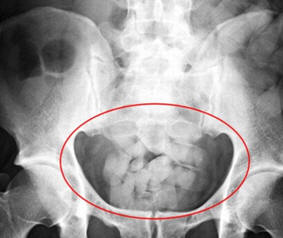

According to court documents, both arrests offered similar stories. Okenwa and Aborishade arrived at Dulles on March 24 and March 30, respectively. Both men were referred for secondary interviews. CBP officers detected inconsistencies in their reasons for visiting the U.S. Both men's stomachs seemed distended and x-rays at local hospitals revealed foreign bodies in their persons. Okenwa passed 88 pellets that weighed 1,769 grams, or 3 pounds, 14 ounces. Aborishade passed 100 pellets that weighed 1825 grams, or 4 pounds, 0.34 ounces.